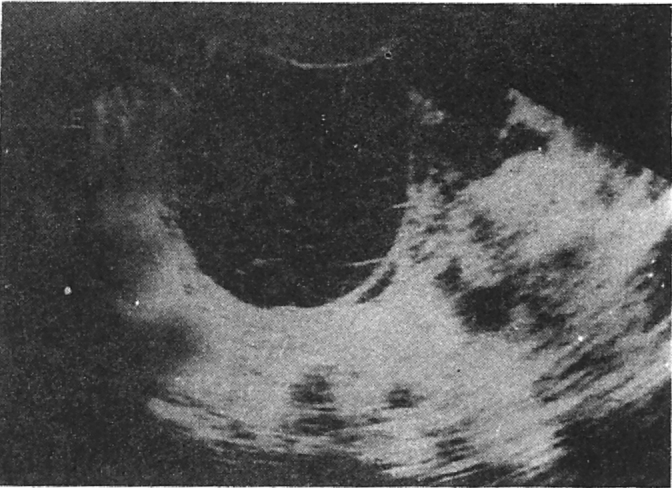

Fig. 5.

Ovarian hyperstimulation syndrome